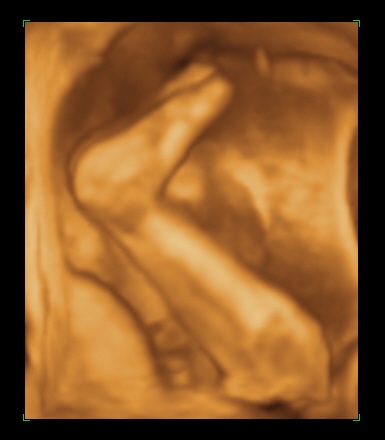

Rólunk: tegnap voltam a dokinál, nagy valószinüséggel kislány a Pötty babánk (de még nem mondta tutira a doki, mert eléggé összezárta a lábikóit)